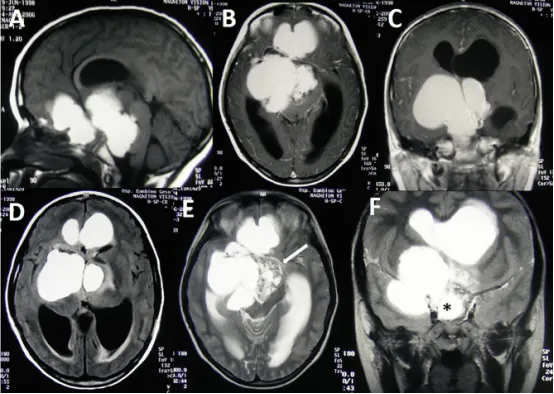

早在20世纪90年代,神经外科学奠基人Harvey Cushing即将颅咽管瘤定性为最可怕的颅内肿瘤。尽管其病理分级仅为WHO I级,发病率亦低于垂体腺瘤,然而病理分级的低度恶性并不等同于临床处置的低...

颅咽管瘤作为儿童常见的颅内先天性肿瘤之一,它的治疗可能会引发多种并发症,手术可能因直接组织操作或缺血而损伤神经结构,放疗则可能引起放射性坏死或血管病变。手术的成功只是小儿...

在儿童神经外科领域,造釉细胞瘤性颅咽管瘤(AC)是个特殊的狠角色它虽被归为低级别恶性肿瘤,却因紧邻视路、垂体、下丘脑等关键结构,让治疗陷入两难:彻底切除可能导致终身内分泌紊...